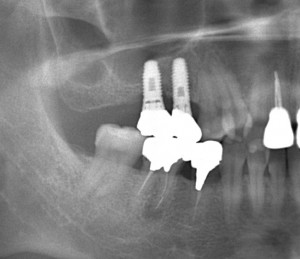

上顎臼歯部のソケットリフトによる骨造成をおこなった症例

上顎臼歯部のソケットリフトによる骨造成をおこなった症例をご紹介します。

K様 30代 女性

上顎の奥歯の方の骨がなく、ソケットリフトを用いて骨造成を行い、インプラントを埋入しました。

術前レントゲン写真です。

インプラント埋入直後のレントゲン写真です。

↑上のレントゲンを見ると、ドーム状に膨らんでいるのがわかります。

被せ物装着した後のレントゲン写真です。

↑最初薄かったレントゲン像が、周囲の骨と一体化し骨化したのがわかります。